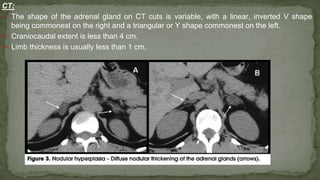

➢ The shape of the adrenal gland on CT cuts is variable, with a linear, inverted V shape

being commonest on the right and a triangular or Y shape commonest on the left.

➢ Craniocaudal extent is less than 4 cm.

➢ Limb thickness is usually less than 1 cm.